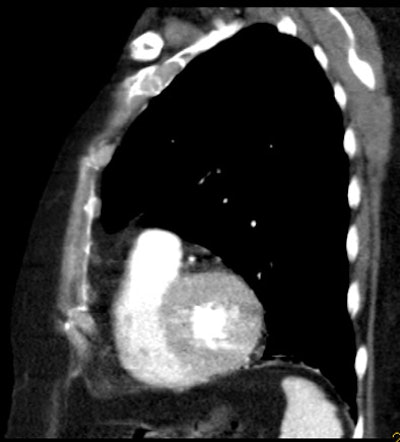

| An 81-year-old woman with acute chest pain and suspicion of acute pulmonary embolism. Short-axis images obtained at end-diastolic (above) and end-systolic (below) phase of the cardiac cycle using ECG-gated 16-slice CT. Right and left ejection fractions were measured at 43% and 41%, respectively. Note the variation of both ventricle volumes and myocardium thickness throughout cardiac cycle. On the same examination, slab MIP oblique reformatted images (bottom) revealed hypodensity in the right pulmonary artery and arteries of the right lower lobe consistent with acute pulmonary embolism. All images courtesy of Dr. Emmanuel Coche. |